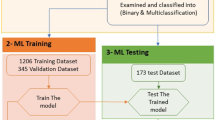

A set of 1370 annotated X-ray images were used to train the Faster R-CNN for object recognition. There were 60,000 iterations and an initial learning rate of 0.0003, which was reduced to 0.00006 after 30,000 iterations.

The AP for implants approached 0.99 after 10,000 iterations (Fig. 2a), indicating that the implants could be detected with high accuracy. The AP for marginal bone loss gradually increased with an increasing number of iterations. When the number of iterations reached 30,000, the AP value fluctuated slightly; it eventually stabilised at 0.47 after 60,000 iterations (Fig. 2b). The mAP of implants and marginal bone loss was 0.73 (Fig. 2c).

The average precision [35] (AP; i.e., the area under the curve) of the implant and marginal bone loss lesion areas, as well as the mean average precision (mAP) of an intersection over unit (IoU) of > 0.5, were calculated. a average precision of implant classification; b average precision of marginal bone loss lesion classification; c mean average precision